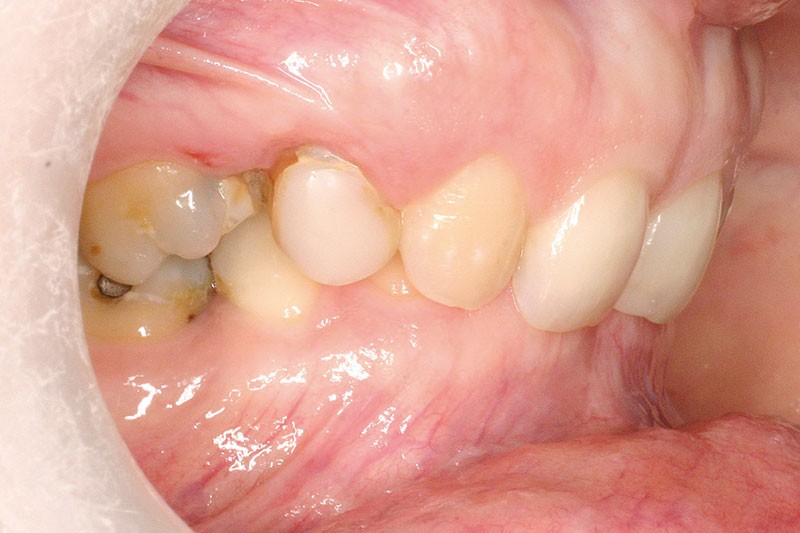

La patiente, âgée de 30 ans, présente des agénésies multiples : 12, 22, 14, 15, 24, 25, 35 et 45 (fig. 1 à 3).

Malocclusion de classe II par rétrognathie mandibulaire dans un schéma squelettique hypodivergent (fig. 4 à 6).

On note une forte supraclusion incisive (fig. 7 à 9).

Un traitement orthodontique a déjà été effectué pendant son adolescence avec un choix de fermeture d’espaces qui a entraîné une linguoversion incisive maxillaire excessive (fig. 10), avec un préjudice esthétique important notamment sur le sourire (fig. 11 à 13).